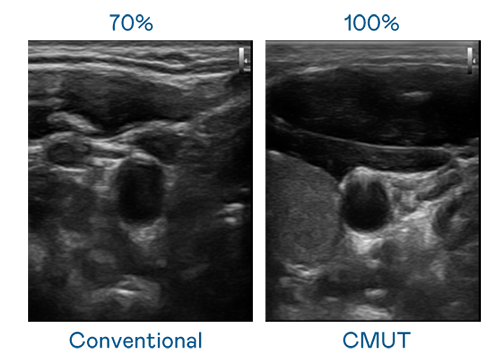

CMUT 技术是一种用电容式微机电元件来产生超音波讯号的技术。与传统 PZT 压电式技术相比,CMUT 频宽增加 30%,更宽频的超音波讯号让影像解析度大幅提升,是实现高影像品质医疗超音波扫描、促进精准医疗发展的关键技术。

大频宽带来超清晰影像

超音波影像的解析度高低,首先取决于探头能发出的讯号频宽。竞技联盟德州 CMUT 可提供高清晰的超音波讯号,提供高频宽、高灵敏度、影像纹理细节更高的超音波影像,协助医护人员缩短影像判读时间及利用精准的医疗影像进行诊断。